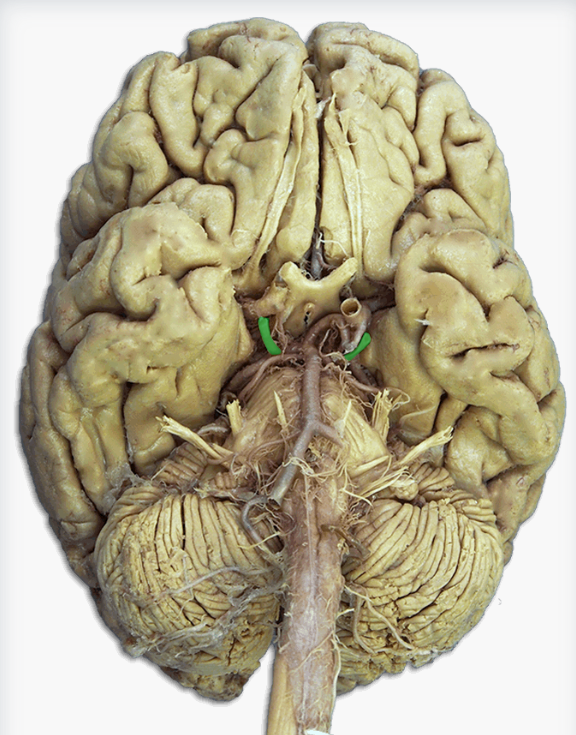

Label this cerebral artery

Basilar artery

Label this cerebral artery

Anterior communicating artery

Label this cerebral artery

Middle Cerebral Artery

Label this cerebral artery

Posterior Cerebral Artery

Optic chiasm

Label this brain structure

Optic tract

Name this brain structure

Label this cranial nerve

Olfactory (CN I) nerve

Label this cranial nerve

Optic (CN II) nerve

Label this cranial nerve

Oculomotor (CN III) nerve

Label this cranial nerve

Trochlear (CN IV) nerve

Label this cranial nerve

Trigeminal (CN V) nerve

Label this cranial nerve

Abducens (CN VI) nerve

Label this cranial nerve

Facial (CN VII) nerve

Label this cranial nerve

Vestibulocochlear (VIII) nerve

Label this cranial nerve

Glossopharyngeal (CN IX) nerve

Label this cranial nerve

Vagus (CN X) nerve

Label this cranial nerve

Accessory (CN XI) nerve

Label this cranial nerve

Hypoglossal (CN XII) nerve